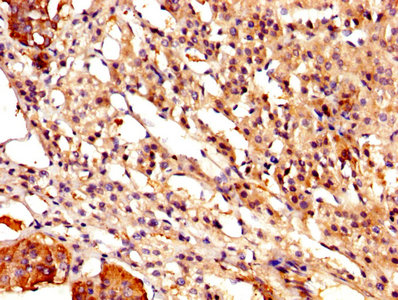

• IHC image of CSB-PA004561YA01HU diluted at 1:500 and staining in paraffin-embedded human lymph node tissue performed on a Leica BondTM system. After dewaxing and hydration, antigen retrieval was mediated by high pressure in a citrate buffer (pH 6.0). Section was blocked with 10% normal goat serum 30min at RT. Then primary antibody (1% BSA) was incubated at 4°C overnight. The primary is detected by a biotinylated secondary antibody and visualized using an HRP conjugated SP system.

• IHC image of CSB-PA004561YA01HU diluted at 1:500 and staining in paraffin-embedded human adrenal gland tissue performed on a Leica BondTM system. After dewaxing and hydration, antigen retrieval was mediated by high pressure in a citrate buffer (pH 6.0). Section was blocked with 10% normal goat serum 30min at RT. Then primary antibody (1% BSA) was incubated at 4°C overnight. The primary is detected by a biotinylated secondary antibody and visualized using an HRP conjugated SP system.